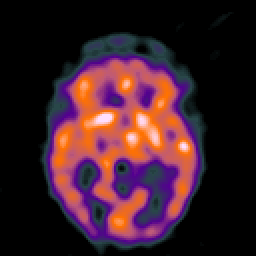

Hypertensive Encephalopathy: MRI/SPECT overlay -- Slice #10

[Home][Help][Clinical] Slice 10